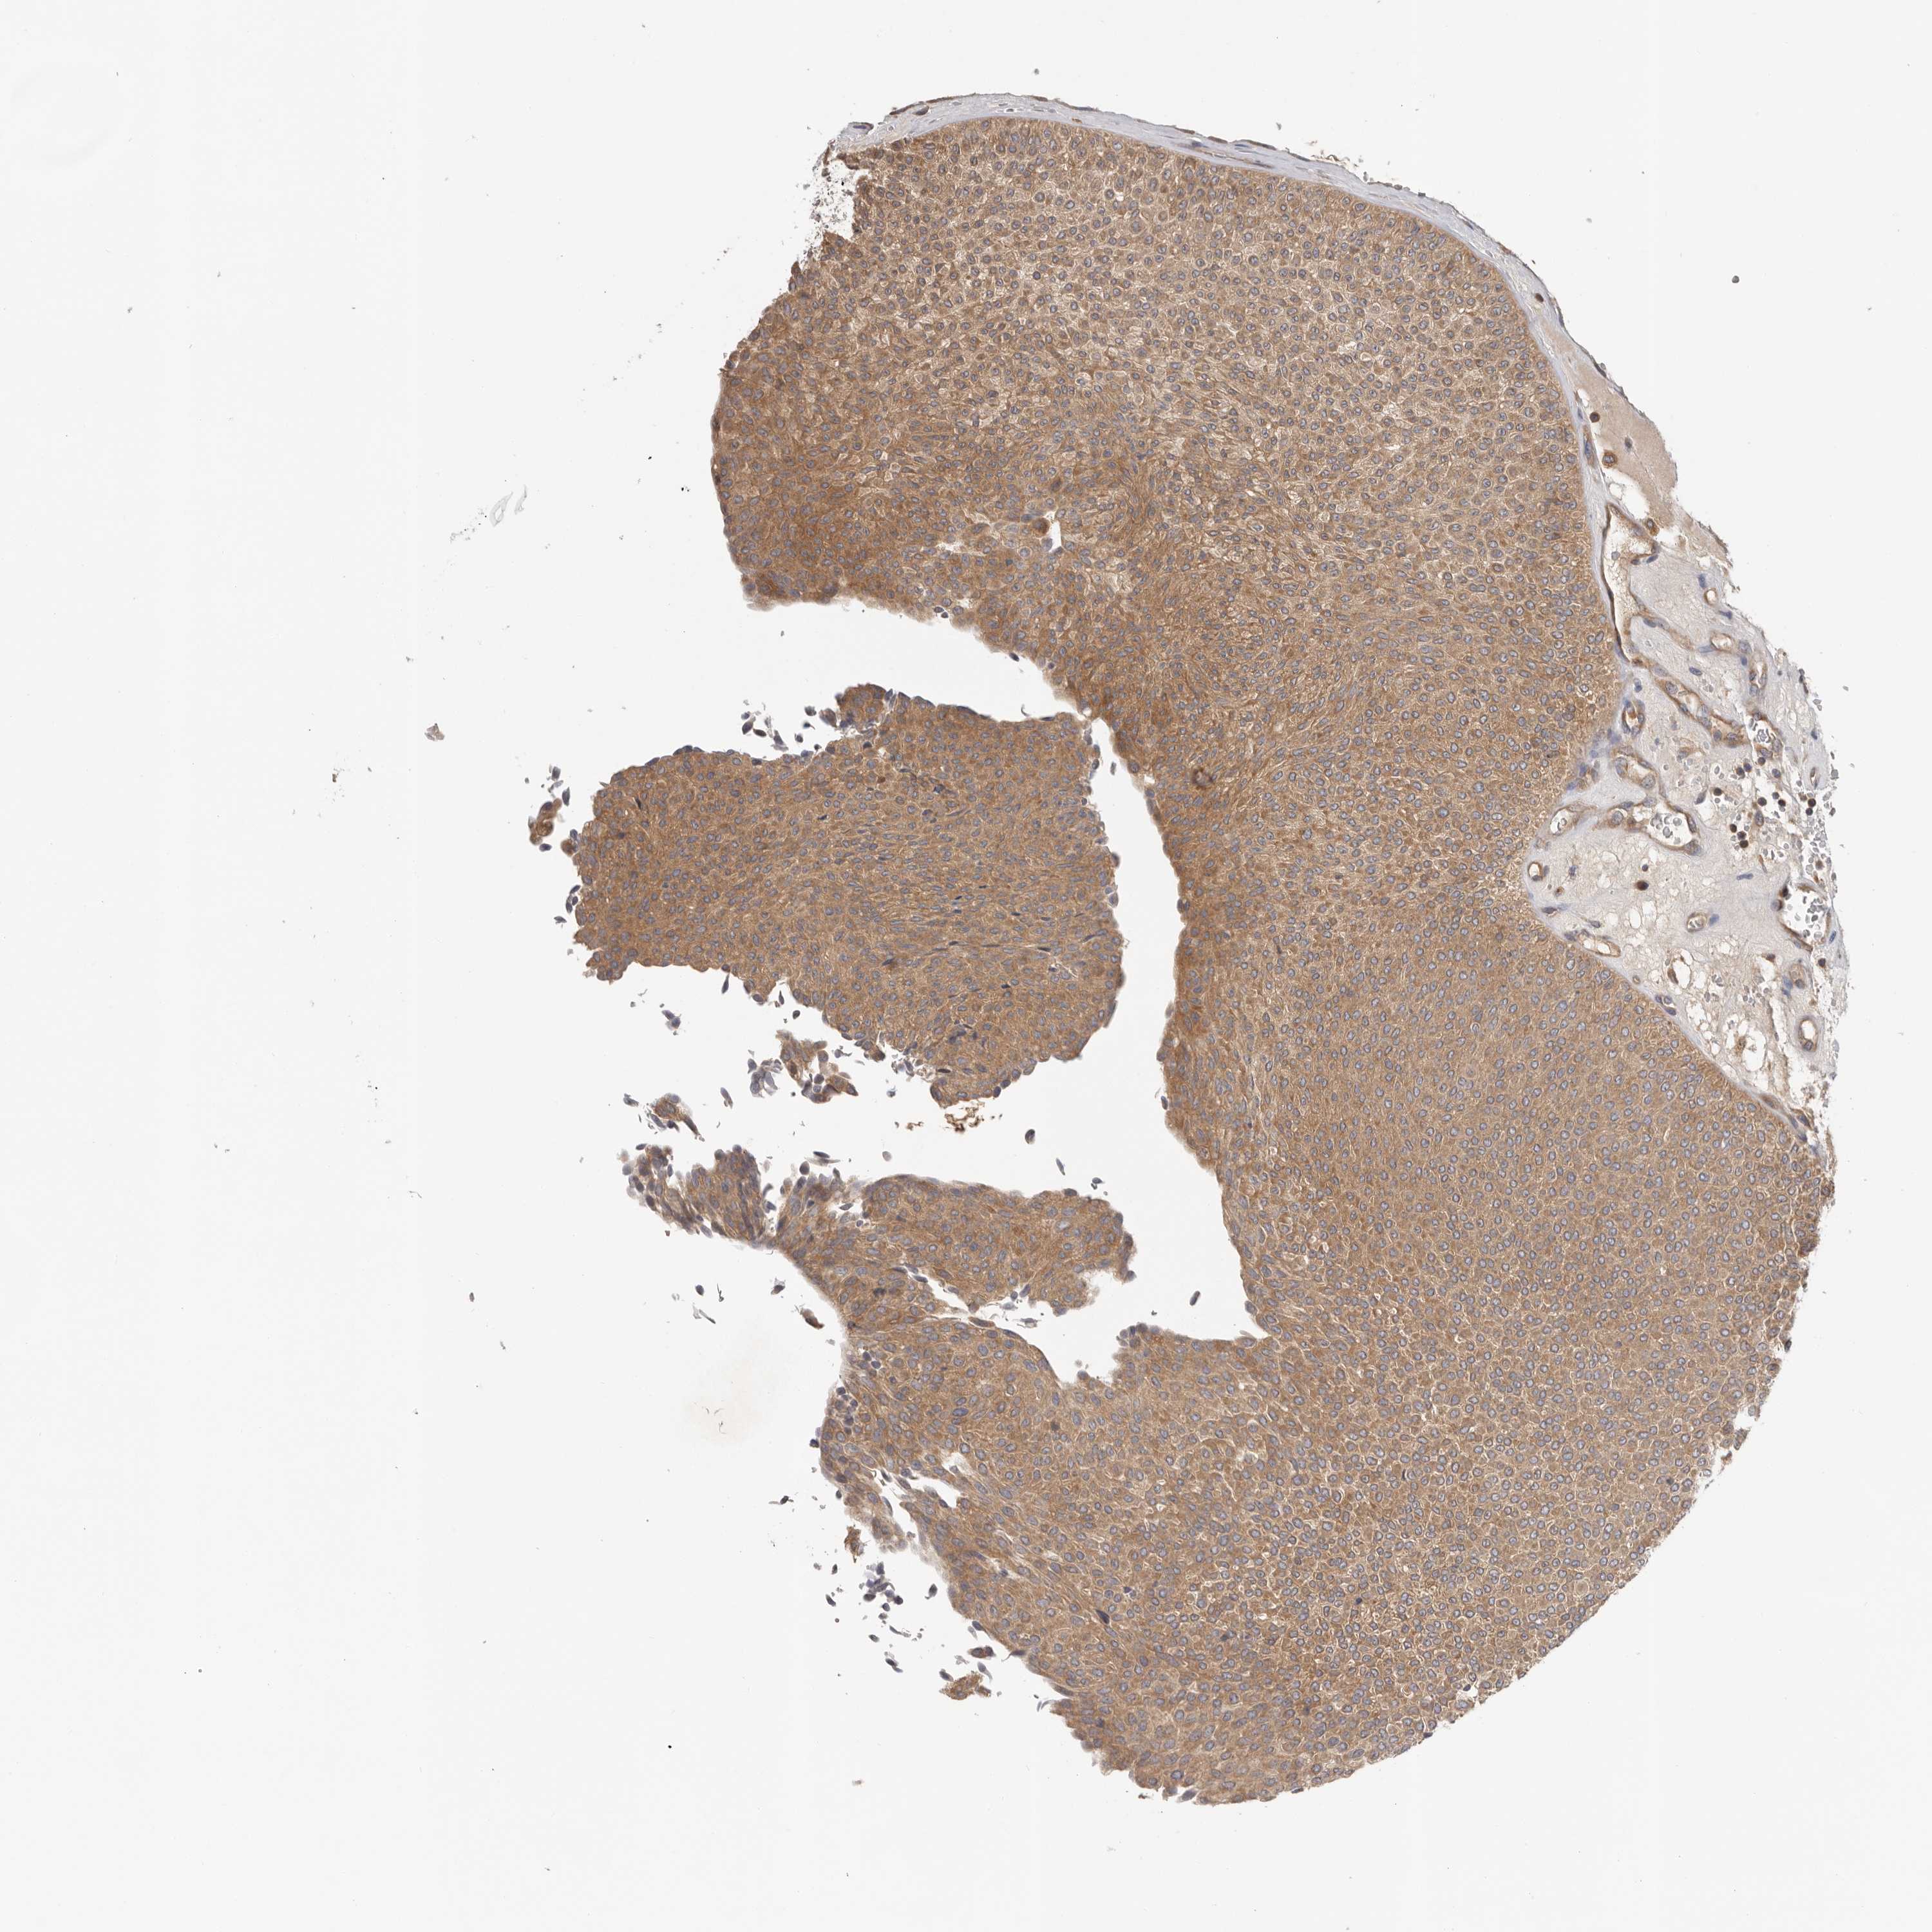

UROTHELIAL CANCER - Protein expressioni

A mouse-over function shows sample information and annotation data. Click on an image to view it in a full screen mode. Samples can be filtered based on level of antibody staining by selecting one or several of the following categories: high, medium, low and not detected. The assay and annotation is described here.

Note that samples used for immunohistochemistry by the Human Protein Atlas do not correspond to samples in the TCGA dataset.

Antibody stainingi

Antibody staining in the annotated cell types in the current human tissue is reported as not detected, low, medium, or high, based on conventional immunohistochemistry profiling in selected tissues. This score is based on the combination of the staining intensity and fraction of stained cells.

Each image is clickable and will lead to virtual microscopy that enables deeper exploration of all samples and also displays staining intensity scores, fraction scores and subcellular localization as well as patient and tissue information for each sample.

Antibody HPA024313

Antibody HPA027983

Antibody HPA028628

Urothelial carcinoma, High grade